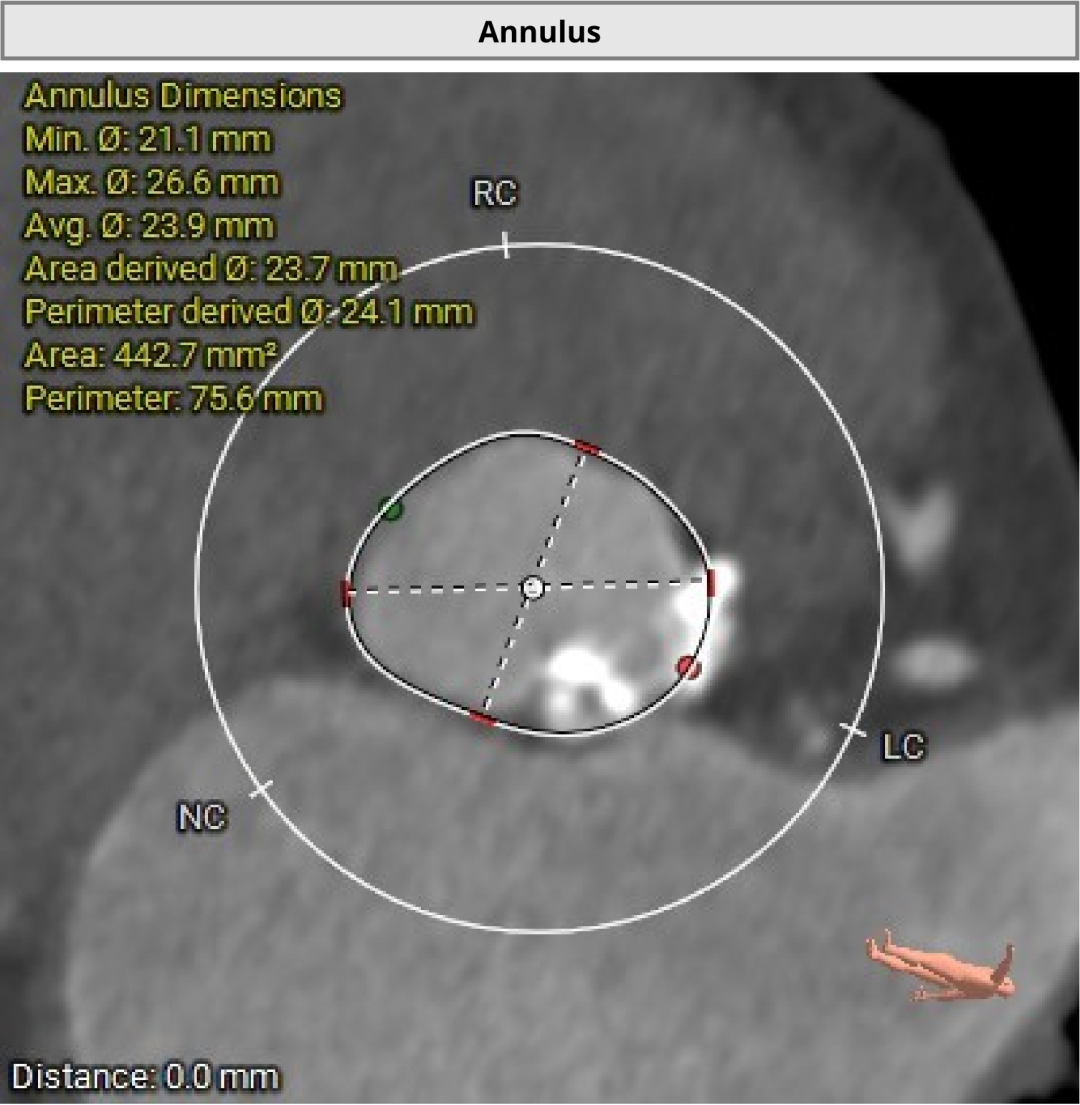

术前CT评估显示,患者瓣膜解剖条件总体具备经导管治疗基础,双侧冠脉阻塞风险偏低。

进一步评估显示,患者瓣膜狭窄程度重,瓣叶钙化明显,左心室腔径偏小,手术中对器械通过、瓣膜释放以及循环稳定性的要求都更高。团队结合术前影像和整体身体状况,制定了周密的介入治疗方案,并做好相关风险预案。

CT评估

瓣膜评估